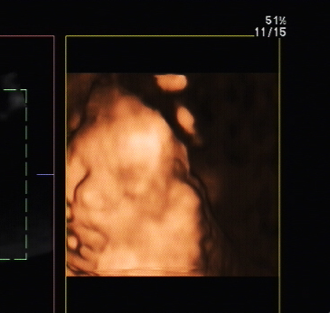

3D Ultraschall mit Hindernissen - Tagebücher aus der Schwangerschaft von Ophelia aus Köln